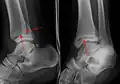

A triplane fracture of the ankle as seen on plain X-ray

A triplane fracture of the ankle as seen on CT

- Triplane fractures are a special type of fracture that involves the immature skeleton. It has a coronal plane in the metaphysis, an axial plane in the physis, and a sagittal plane in the epiphysis.[14]